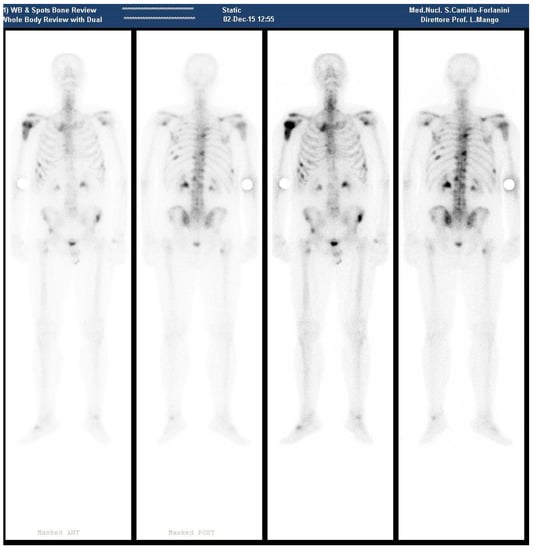

In December of the same year, the patient presented at our department. A new bone scan revealed hyperaccumulation on the proximal epiphysis and diaphysis of right humerus; left scapular glenoid; upper margin right scapula; rear bow of XII, IX, VI right rib, IX, VIII, VI left rib, front bow VI and VII right rib, IV and VII left ribs; D6, D9, D10, D12, L1, L2 vertebral body; anterior superior iliac spines; upper corner of the right acetabular roof; left sacroiliac synchondrosis; right femoral pertrocanteric region (Figure 1).

Figure 1.

(December 2015—Bone scan pre 223RaCl2 Therapy, showing several metastatic sites as described in the text).